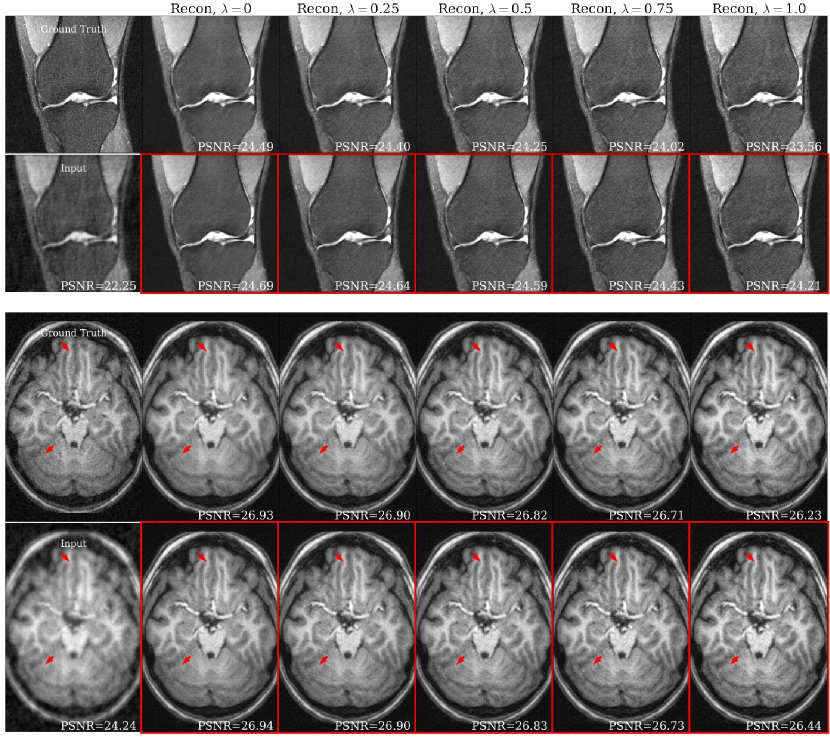

Fig. 3 shows metric performance for brain data. Each panel shows Unet and HyperRecon-L performance for the specified metric across λ𝜆\lambda values. Similarly, Fig. 4 shows metric performance for knee data on three different reconstruction tasks. We observe very close matching of performance across all metrics between Unet and HyperRecon-L models, indicating that the hypernetwork is able to generate the optimal weights for the entire hyperparameter space. For downstream brain segmentation, the optimal λ𝜆\lambda for maximizing Dice is around 0.250.250.25. With HyperRecon-L, this optimal point can be easily obtained with a single model.

Fig. 5(a) shows representative brain and knee slices for the CS-MRI task, and Fig. 5(b) shows zoomed-in versions of the red arrow regions for the brain slices. We notice a significant visual similarity between the same hyperparameters for Unet and HyperRecon-L models. In general, a higher weight on MAE tends to lead to more blurry and smoother reconstructions, while a higher weight on SSIM tends to lead to more noisy reconstructions with more high frequency content. In addition, MAE tends toward less contrast between hypo-intense and hyper-intense regions, whereas SSIM accentuates this contrast more. With baseline models where 𝝀𝝀\bm{\lambda} must be chosen before training, these variations would be completely missed and end users would be stuck with one reconstruction. Additional slices for CS-MRI, denoising, and superresolution tasks are presented in the Appendix.

(a)

(b)

Figure 5: (a) Representative slices for SL on CS-MRI task with 8-fold under-sampling. Ground truth and input images are denoted in the first column. Top row are baseline Unet reconstructions with varying λ𝜆\lambda. Bottom row (red) are HyperRecon-L reconstructions with varying λ𝜆\lambda. PSNR values in reconstructions provide a basis of comparison between Unet and HyperRecon-L reconstructions of the same λ𝜆\lambda. Brain slices are cropped to show detail. Arrows indicate corresponding points where the difference between reconstructions can be appreciated. (b) Representative brain patches for HyperRecon-L, centered around red arrows.